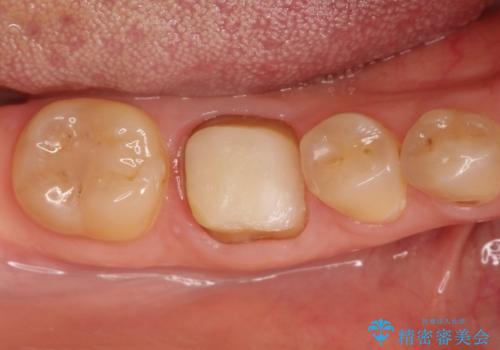

【精密根管治療】間違った根管形成→パフォレーションリペアによる修復

- 他院で根管治療を行なっていたが、以下のような不信感があり転院されてきた患者様です。

根管内を見てみると、近心根は本来の根管とは違うところを削られて髄床底でパーフォレーションを起こしていました。

また、遠心根でも本来の根管とは逸脱した方向に根管形成されていましたが、修正し充填を行っています。